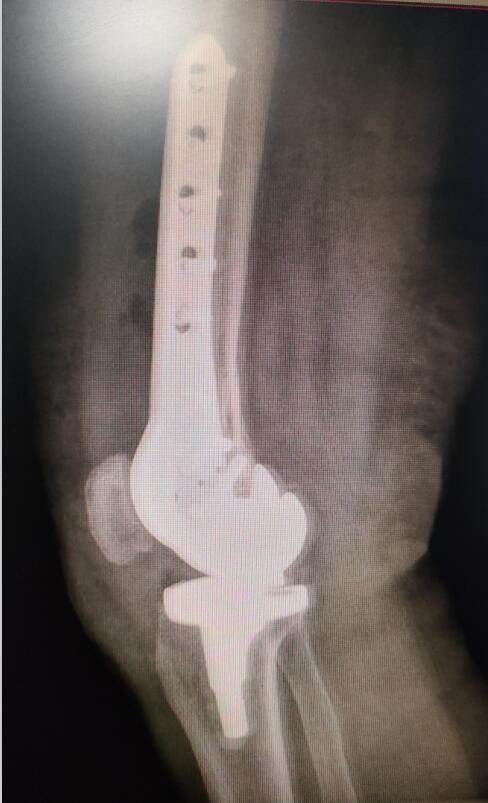

手術(shù)后照片